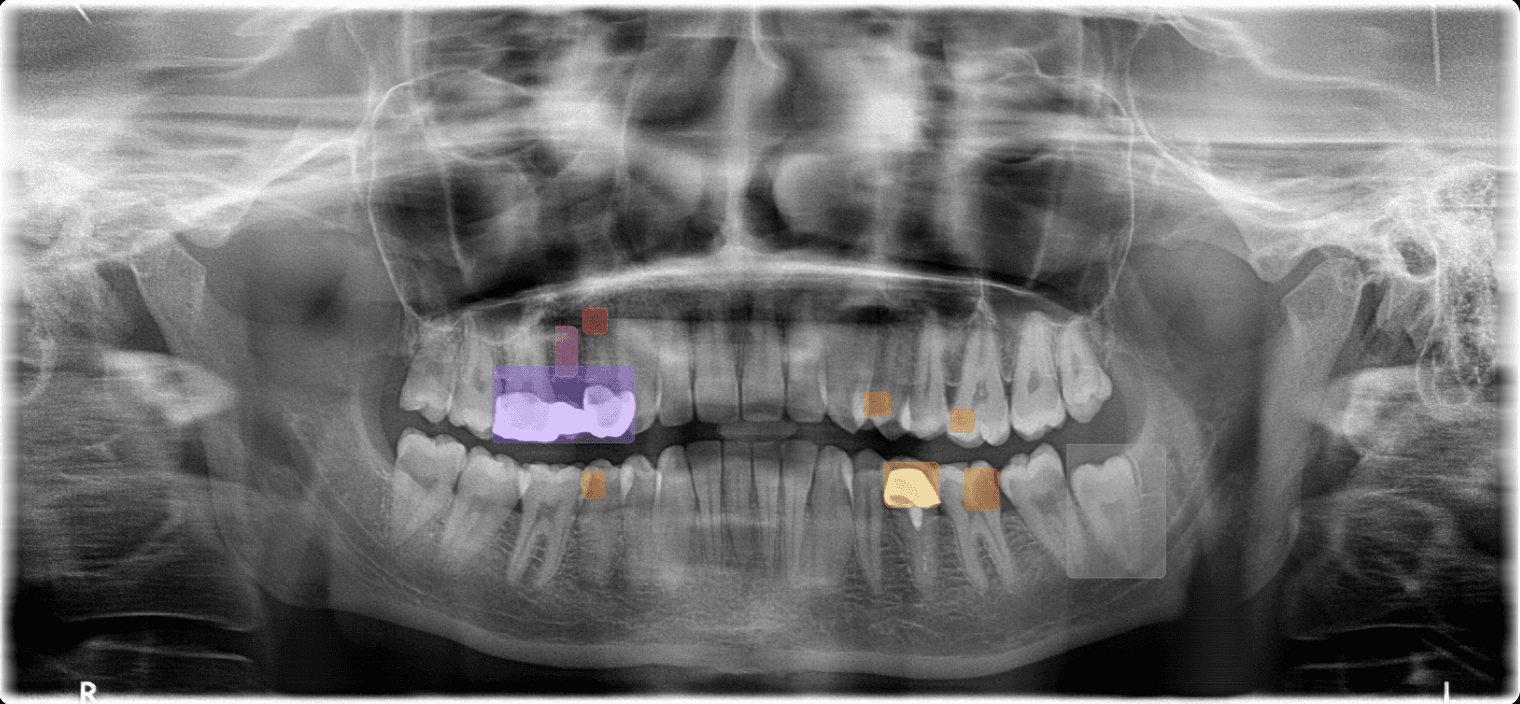

Candidate observation

Anatomy marker

Bone segmentation

Candidate observationTooth 36

AI 2DClinician review85%

Accept

Reject

Edit

Candidate observations and anatomy markersClinician review required

Panoramic (OPG)Bone levels, impacted teeth, sinuses, and broad candidate-observation review across all quadrants